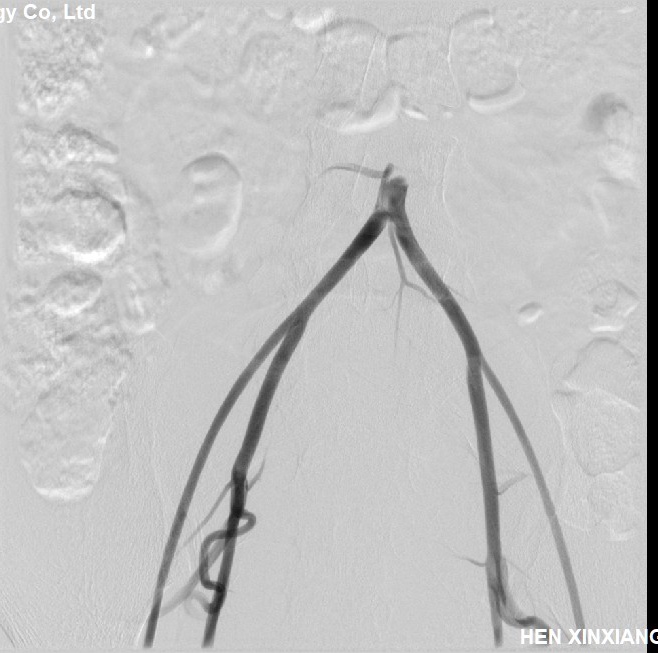

常规股动脉入路,穿刺时双侧股动脉搏动非常弱,两个人轮流尝试好几次才坚难穿刺右股动脉成功,置入股动脉鞘,造影确认在股动脉,但是发现股动脉比较细,没过多思考原因,直接泥鳅导丝带造影导管上去准备造影,结果发现到腹主动脉下端导丝导管过不去,造影发现腹主动脉近髂动脉处闭塞了!

用猪尾巴管再次造影确认腹主动脉确实闭塞了,这时明白为什么股动脉搏动弱不好穿刺了,赶紧换通路,穿刺右桡动脉!可是腹主动脉为什么闭了?紧急请心外科会诊,一打电话心外科说2018年在心外做瓣膜置换术时已经闭了,考虑大动脉炎!